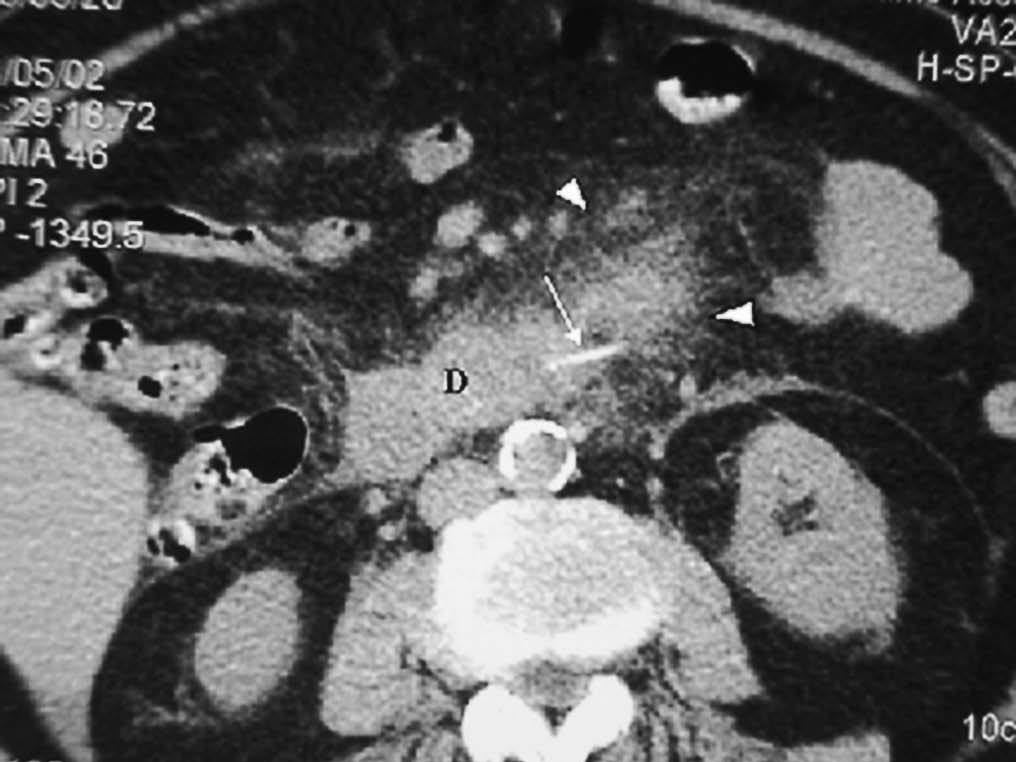

La forma más frecuente es la ausencia de rotación intestinal, que implica importantes alteraciones anatómicas valorables tanto en la ecografía como por la TC. Los principales hallazgos radiológicos son: alteración en la posición del duodeno, que no pasa entre la aorta y la arteria mesentérica superior (AMS); la localización en el hemiabdomen derecho de las asas de intestino delgado y en hemiabdomen izquierdo las de intestino grueso, y una verticalización o inversión de los vasos mesentéricos respecto a su posición normal, quedando la AMS a la derecha y la vena mesentérica superior (VMS) a la izquierda1,2 (fig. 1).

Fig. 1--Malrotación intestinal. (A) y (B) Tomografía computarizada con contraste oral e intevenoso mostrando inversión de la arteria mesentérica superior (AMS) (punta de flecha) y la vena mesentérica superior (flecha). La tercera porción duodenal (D) no cruza la línea media entre la aorta y la AMS, localizándose las asas de yeyuno a la derecha.